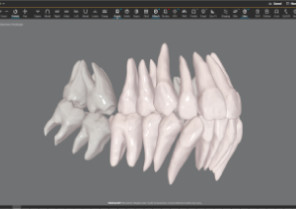

Shows you real root renderings and bone visualizations based on actual scan data.

Simulates root movement along with tooth movement.

Roots only

Roots only